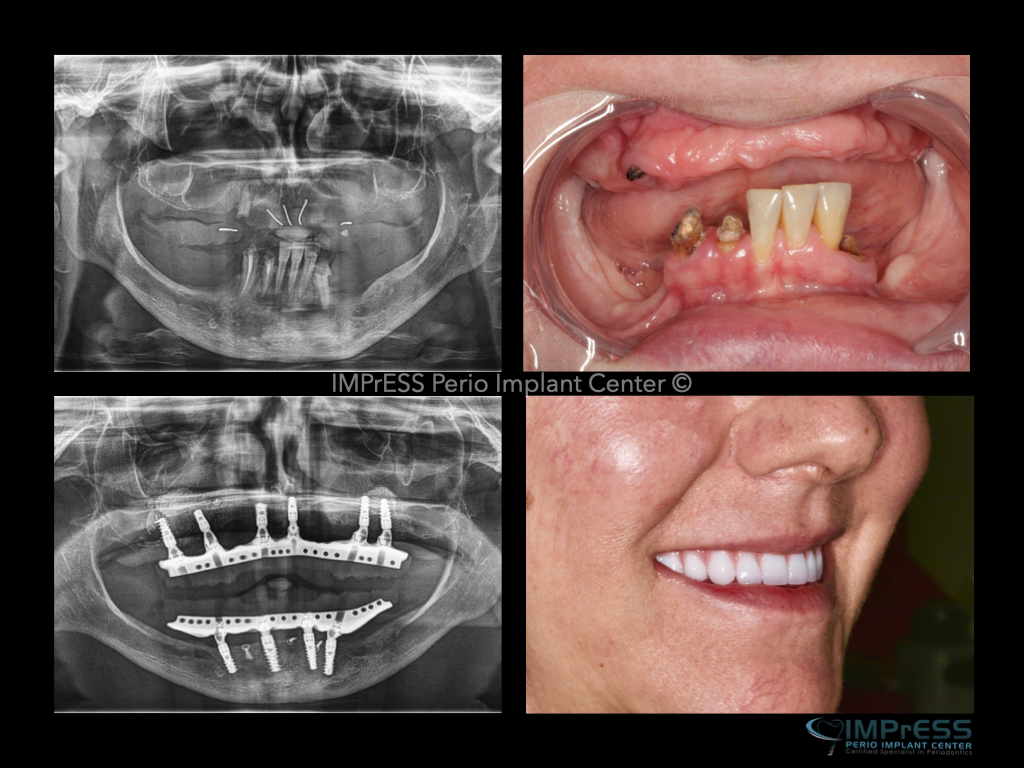

All on X implant Full Mouth Implant Reconstruction All on 4 Implants IMPrESS Perio Implant Center Vancouver Burnaby Periodontist Prosthodontist Implant Specialist Dr. Noroozi Periodontist Implant Specialist